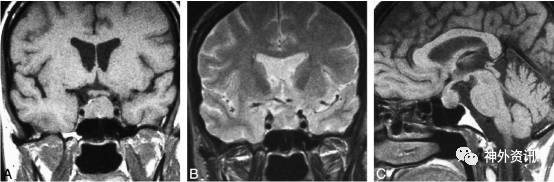

进一步行垂体MR扫描,显示“鞍上一结节状异常信号灶,呈等T1等T2,增强后明显均匀强化,与垂体柄分界不清,视交叉略受压,三脑室底部略受压。垂体变扁呈弧形状紧贴鞍底,增强后均匀强化。考虑鞍上偏后方富血供肿瘤。鞍上占位,脑膜瘤可能性大(图2)”。

图2. 垂体 MRI 检查示:鞍上一结节状异常信号灶,呈等 T1 等 T2,增强后明显均匀强化,考虑鞍上偏后方富血供肿瘤,脑膜瘤可能大。